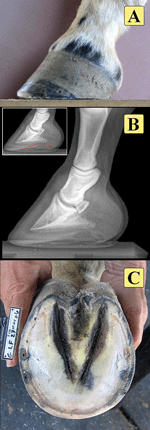

In the ideal situation, our horses come with perfect conformation and great hooves. A good hoof should be well set under the ‘bony column’, have good horn quality, support length, good sole depth and arch definition (Fig 1). In reality, most horses have some conformational flaws and with less than perfect hooves. Before I dive into the most common hoof problems, I want to stress the importance of implementing a proper hoof care routine. Most common hoof problems can be helped, and sometimes completely avoided, if some simple steps are followed. For instance, horse’s weight should be kept within a reasonable range. Ensure that you discuss every horse’s history, including its situation, problems, and usage in order to do the best for your clients.

Fig 1. A hoof with good conformation. The radiograph in 1B shows a well-formed arch, which supports the pedal bone in a good internal stance.